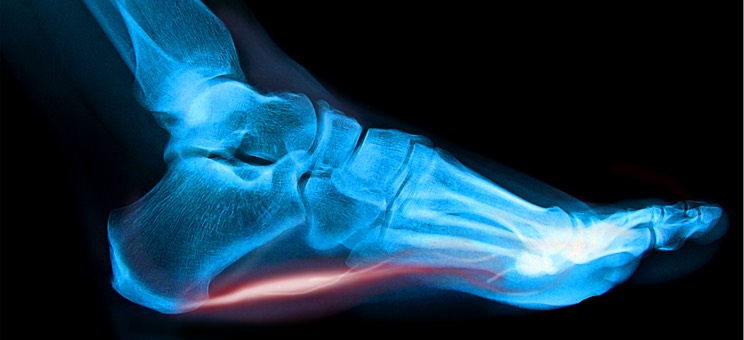

Plantarfasciitis xray with red ligt

The typical presentation is sharp pain with weight bearing at the front part of the calcaneus.  X-rays can sometimes show a heel spur, but there is no relationship between a heel spur and plantar fasciitis, that is people can have a heel spur and not have any symptoms, and people can have plantar fasciitis and not have a heel spur.  The heel spur is not the problem.